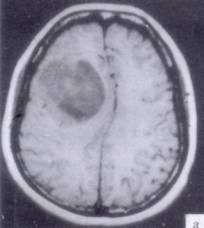

问题 病历摘要:??患者男性,52岁。头痛伴呕吐2月,呕吐呈喷射性。既往身体健康。体检:神清,表情淡漠,反应迟钝,双眼底视神经乳头明显水肿,左鼻唇沟稍浅,左腹壁反射减弱,左上下肢肌力4级,左Babinski征(-)。 根据病史、MR结果,首先考虑哪种诊断?提示:患者行头颅?MR检查(见图)

选项 A.右额叶胆脂瘤 B.右额叶转移瘤 C.右额叶胶质瘤 D.右额叶淋巴瘤 E.右额叶脑膜瘤 F.右额叶脑脓肿 G.右额叶炎性肉芽肿

答案 C